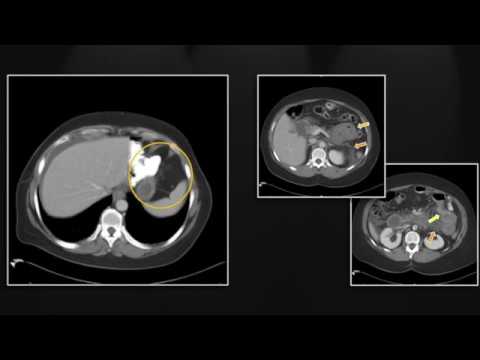

Emergent Complications of Bariatric Surgery | Interesting Radiology Cases